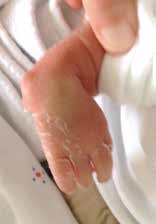

Aus handchirurgischer Sicht muss schließlich geprüft werden, ob eine Operation indiziert ist. Dazu muss die Gesamtsituation betrachtet werden. Sind z. B. weitere Fehlbildungen an anderen Gliedmaßen oder Organen vorhanden? Wie dringlich ist die Versorgung der anderen Fehlbildungen? Vorrangig ist stets die Behandlung lebenswichtiger Organe wie z. B. des Herzens oder der Speiseröhre durch die entsprechenden Fachdisziplinen. Weiterhin wird geprüft, ob eine Mitarbeit des Kindes während der postoperativen Nachbehandlung erforderlich ist. Diese ist gegebenenfalls erst zu einem späteren Zeitpunkt motorisch und von seiner geistigen Entwicklung her möglich. Sind Eingriffe am Skelettsystem erforderlich, sollten diese keine Wachstumsstörungen hervorrufen. Der natürliche Verlauf mit möglicher Adaptation sollte immer gegenüber einer operativen Behandlung abgewogen werden, denn Kinder lernen in der Regel spontan ihre Finger‑, Hand- und Armdeformität funktionell einzusetzen. Betroffene Patienten entwickeln häufig eine große Geschicklichkeit trotz vorhandener Fehlstellung (Abb. 1). Für eine ästhetische Korrektur darf keine Funktion verschlechtert werden 4.